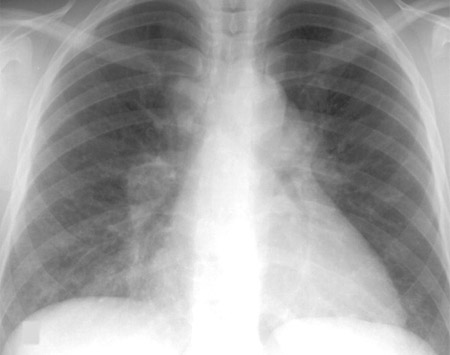

Aparência da silicose à radiografia torácica: existem pequenas opacidades arredondadas, começando inicialmente nos lobos superiores e, com a evolução, esses nódulos menores se conglomeram e formam opacidades grandes (fibrose maciça progressiva). Diferentemente da exposição aos asbestos, não há alterações pleurais observadas na radiografia torácica, embora a fibrose pleural possa ser observada em um espécime patológico da silicose.

[Figure caption and citation for the preceding image starts]: Radiografia torácica da fibrose maciça progressiva devida à exposição à sílica ou carvãoDo acervo pessoal do Kenneth D. Rosenman, Michigan State University [Citation ends].